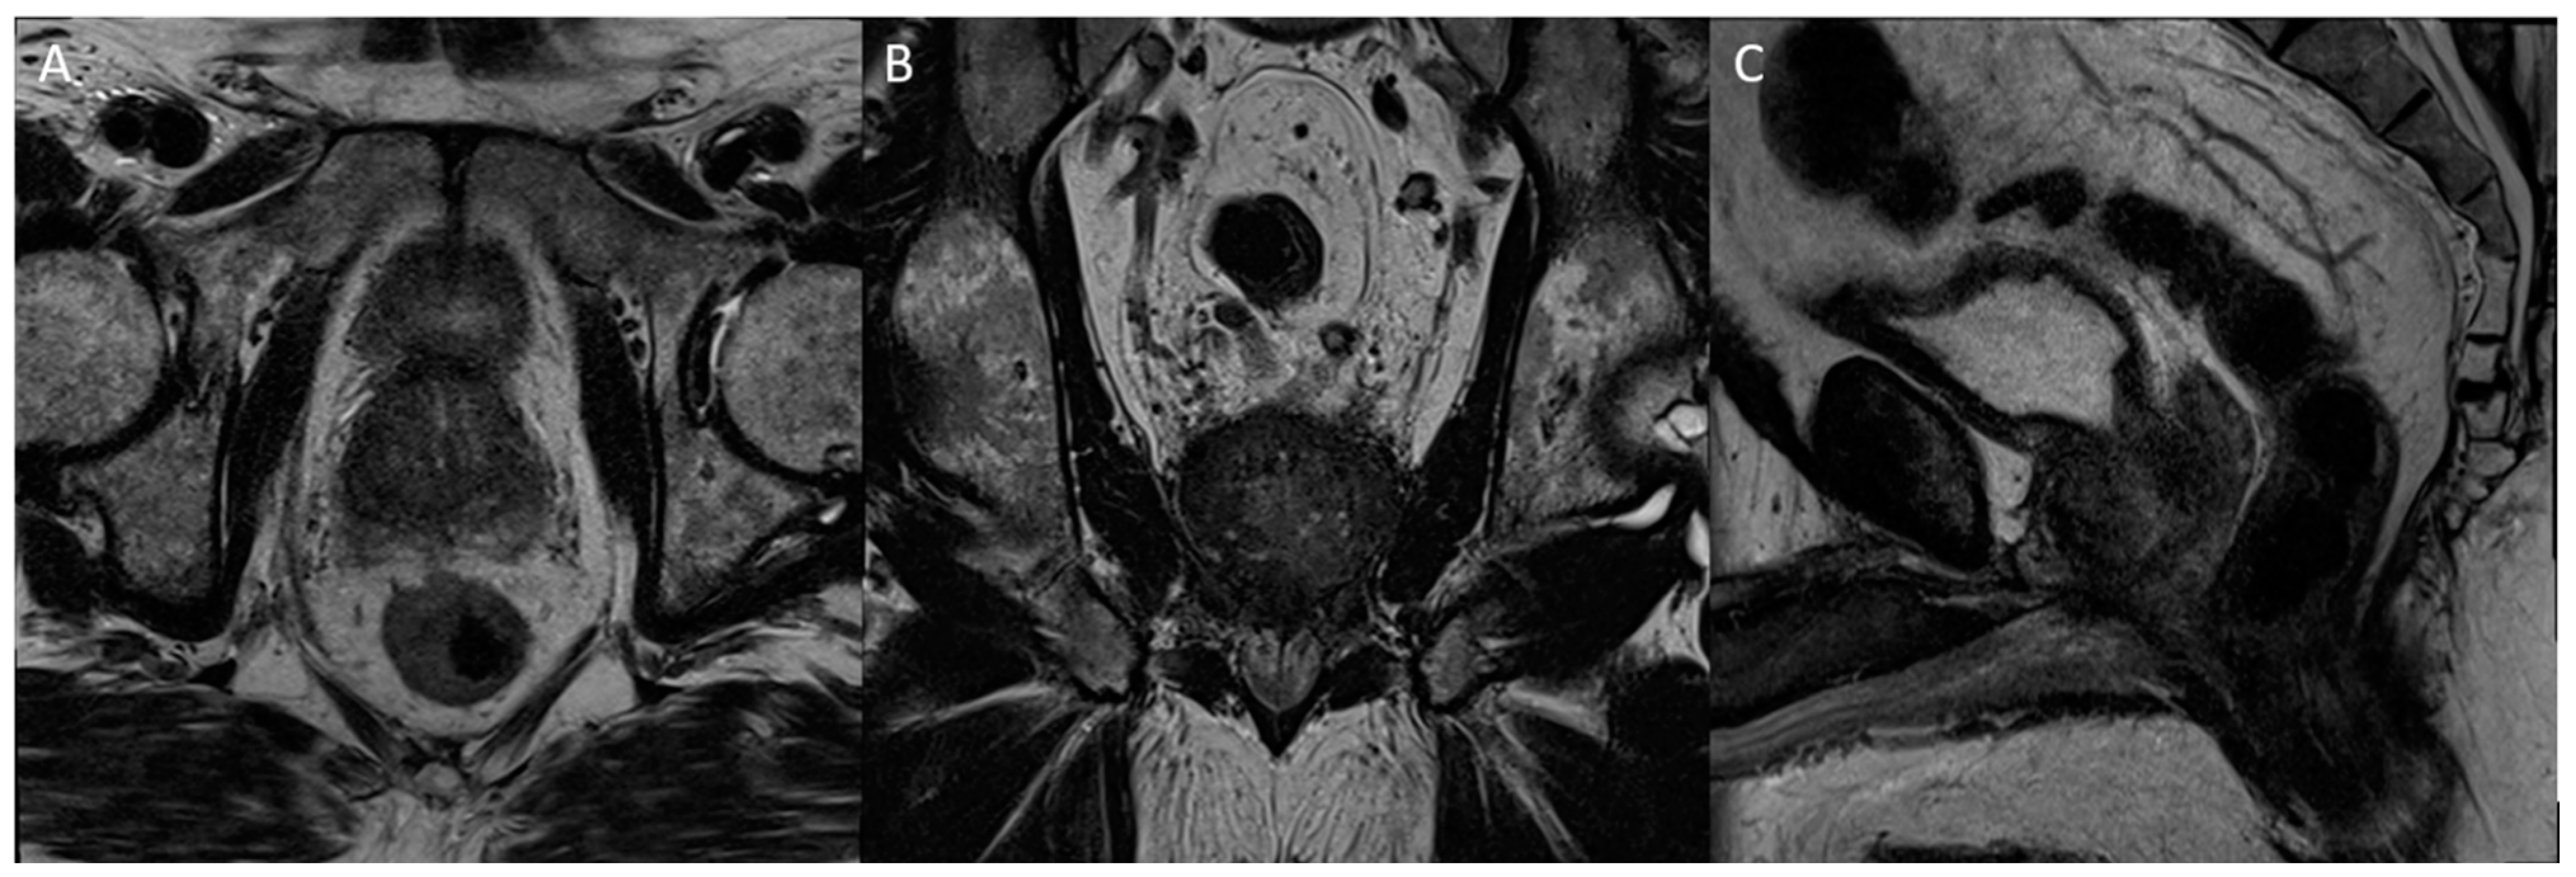

Figure 9. Axial (A), coronal (B), and sagittal (C) T2 images of the irradiated prostate, which demonstrate the loss of features and typical demarcation as well as overall T2 hypointensity, comparable to fibrosis expected post treatment.

Radiation therapy is a treatment modality that can be offered to select patients who seek a non-invasive approach to the treatment of their prostate cancer. The most common form of radiation therapy is external beam radiation therapy (EBRT), in which radiation is delivered to targeted tissues from an outside source through the skin. Brachytherapy is another commonly used method of delivering radiation to cancerous prostate tissue that involves the ultrasound-guided transperineal implantation of tiny radioactive seeds into the prostate. Both temporary or permanent implants, including low dose rate (LDR) and high dose rate (HDR) implants, are another option, which deliver radiation over the course of two months or less than an hour, respectively. The appearance of the prostate following radiation therapy is variable and also potentially confounded by concomitant androgen deprivation therapy being given, but the gland will often appear diffusely T2 hypointense, often combined with the loss of normal features and the demarcation of the peripheral and transition zones (Figure 9).